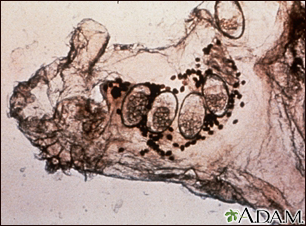

En esta microfotografía aparece el ácaro responsable de la sarna, junto con sus huevos y heces. Los ácaros excavan túneles dentro de la piel, en donde depositan sus huevos y heces. La infestación por sarna produce un prurito intenso que induce al rascado y produce lesiones en la piel (excoriaciones). Sin tratamiento, la enfermedad puede perdurar por muchos años, razón por la cual ha sido llamada "prurito de los siete años".